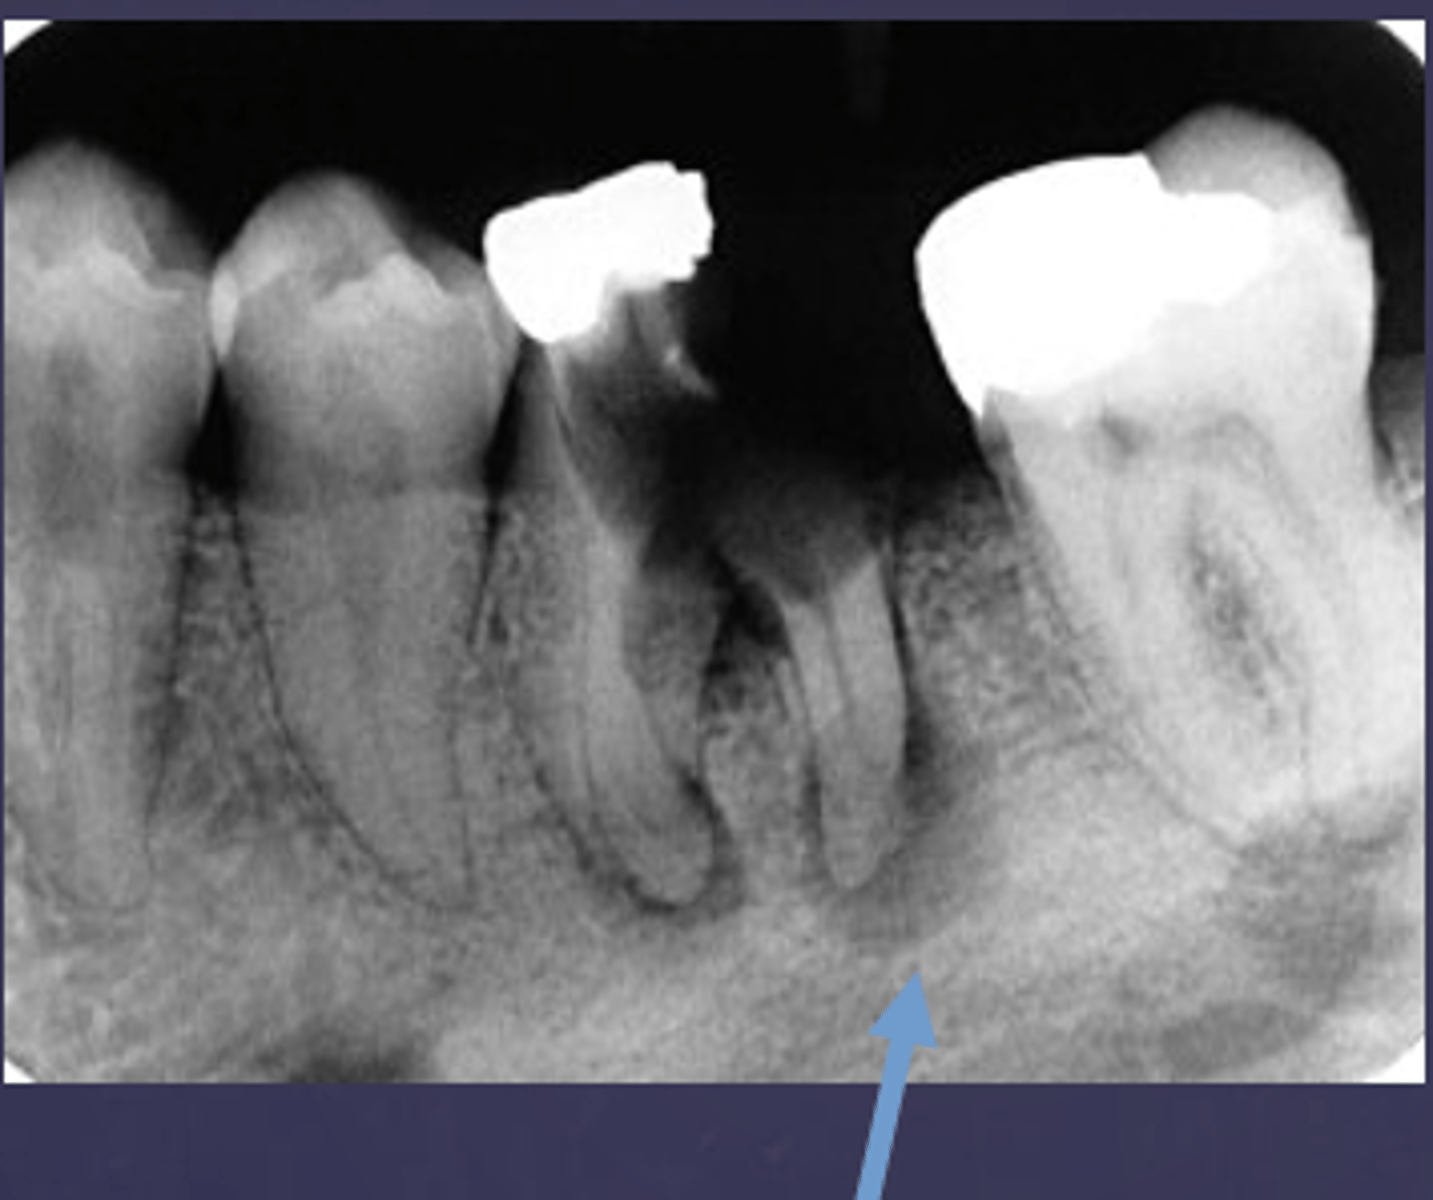

What type of change is seen in this radiograph?

early change (apical periodontitis #30)